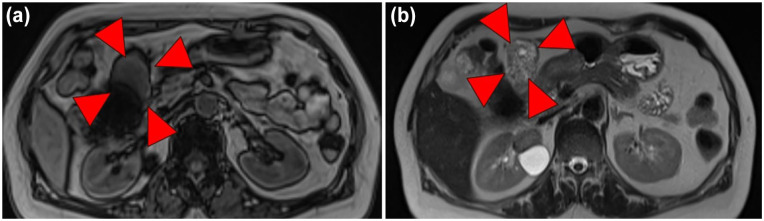

Neuroendocrine cells are distributed throughout the body's organs, though neuroendocrine neoplasms are primarily documented in the gastrointestinal tract and pancreas, with rare occurrences elsewhere. Herein, we report a case of primary neuroendocrine tumor of the omentum (omental NET) that was incidentally detected as an omental mass during preoperative screening for colorectal cancer. The patient, a 66-year-old woman, with abdominal pain and decreased oral intake, leading to a diagnosis of obstructive colorectal cancer with a large, 55 mm, mass around the gastropyloric region, which was discontinuous with the gastrointestinal tract. After the placement of a colonic stent at the site of the ascending colon cancer to decompress the colon, a laparoscopic right hemicolectomy was performed, simultaneously excising the mass. Postoperative pathology revealed a neuroendocrine tumor (NET). Subsequent examinations detected no other lesions of suspected primary disease and postoperative somatostatin scintigraphy found no other lesions, establishing a diagnosis of omental NET. The rarity of omental NETs is attributable to the absence of neuroendocrine cells in the omentum. Moreover, solid tumors originating primarily from the omentum are very rare, making preoperative diagnosis difficult; therefore, postoperative pathology should be utilized. We presented a very rare case of omental NET, previously reported only once in the literature, and believe that complete resection with minimal invasiveness should be performed for treatment of this malignancy. In addition, we emphasize the need for continued patient follow-up.

Abstract Image